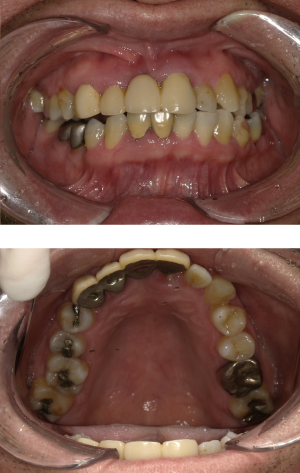

インプラント治療(左上5ソケット・GBR 右上2左上13GBR)

| 年代・性別 | 50代・男性 |

| 主訴 | 入れ歯だと咬めなくてつらい。 |

| 部位 | 上顎②1①2③4⑤Br |

| 治療期間 | 約9ヶ月 |

| 費用 | ¥1,794,100(税込) |